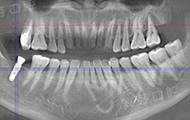

在陆续往返深圳复诊的过程中,也顺便治疗了其他的牙齿,服务品质也是一如既往的好。如今牙齿好了,朋友都说我好像更开朗了,人也感觉年轻很多,我更希望以一个精神饱满的状态来,也碰上了麦芽的周年庆,来看牙的人很多,还好提前跟客服约好了时间。给我种牙的邢博说,种植牙术后的维护也很重要,恢复的很好。当然从广州又再一次来到深圳,我更有心情多品尝深圳的美食。

经过医护人员的严密术前检查和准备工作后,顺利进入了三通道无菌手术室,接受种植博士专家团此前为其量齿定制的全数字化精确种植牙手术,一颗牙种出来真的只需要5分钟,我还没有任何感觉,医生说已经种好了,不得不感叹科技技术发展快、医生技术高超,而且第一次种牙就赶上了“工程”行动,非常幸运,对我们普通百姓来说"工程"援助非常实在,希望"工程"启动能帮助更多的人,毕竟缺牙人很多,祝愿大家都能像我一样在麦芽口腔种好牙,享口福。"